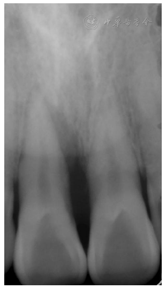

11牙冠完整,扣(-),Ⅰ度松动,唇侧牙龈约牙根中部位置膨隆呈半球型,唇侧牙周袋溢脓,唇侧近中及中央位点PD> 10 mm,余位点PD 2~3 mm。X线根尖片示:11近中牙槽骨环绕牙根牙周病样角型吸收达根尖,远中牙槽骨未见明显异常,见图1。CBCT示:11唇侧近中牙槽骨环绕牙根缺损自冠方达根尖,根中段疑似根折影像,见图2。